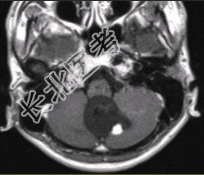

- [材料题] 男性,20岁。恶心、呕吐3d,剧烈头痛加重1d入院。MRI显示小脑下蚓部长T₁、长T₂信号影,病变可见结节状明显强化,如下图。